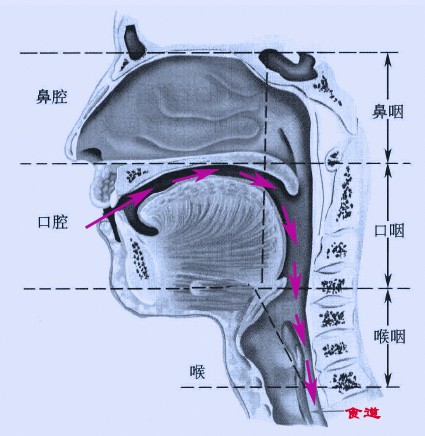

卡了鱼刺,首先应该大概判断一下卡的具体位置,感觉喉结以上疼痛的位置都还太好办,一般这个情况常见于扁桃体、舌根、会厌谷等部位,可以张口自己照镜子看一下,运气好的话能够找到扁桃体上的鱼刺,用筷子自行取出,如果看不到就不要想其他办法了,上医院吧,有时候很小的鱼刺不通过扁桃体的仔细观察和探查根本发现不了。

如果医生发现扁桃体没有鱼刺,就可能会让做喉镜了,喉镜一般可以看到大部分的鱼刺,也同时可以通过镜子取出能看到的鱼刺,做之前一般会喷麻药,所以一般不用太紧张。

感觉在喉结以下喉镜又看不到的鱼刺就有点麻烦了,可能卡在食道某一个位置,这就需要食道镜或者胃镜进行检查了,也可以行CT,毕竟医生也是肉眼凡胎,透视不了,胃镜的话可以一路看到胃,顺便可以看看你的胃功能如何。食道里的鱼刺不是很好取,需要评估位置风险,如上所说,卡在危险的地方,可能有钱也保不了命。但是,只要不是在危险的地方,医生还是会比较顺利的取出来的。